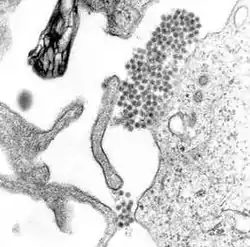

Micrografía de microscopio electrónico mostrando el virus causante de la fiebre hemorrágica del dengue | ||

El dengue es producido por un virus del grupo de los arbovirus (llamados así porque son transmitidos a través de artrópodos hematófagos), familia de los Flaviviridae, género Flavivirus. La partícula viral tiene forma esférica y mide entre 30 y 50 nm. Posee una envoltura proteica (principalmente E y M) que la cubre por completo. El material genético se encuentra contenido en un nucleocápside circular, y entre este y la cubierta se encuentra una bicapa lipídica que es formada a partir de lípidos extraídos de la membrana celular de la célula huésped. El genoma se compone de una sola cadena de ARN de tipo lineal, sentido positivo y gran variabilidad. El virus es altamente inestable en el medio ambiente, inactivándose con el calor, desecación y desinfectantes que contengan detergentes o solventes lipídicos.

El virus del dengue, al igual que otros flavivirus, contiene un genoma de ARN rodeado por una nucleocápside de simetría icosaédrica, de 30 nm de diámetro, la cual está constituida por la proteína C ―de 11 kd― y una envoltura lipídica de 10 nm de grosor asociadas a una proteína de membrana (M) y otra de envoltura (E), que da lugar a las proyecciones que sobresalen de la superficie de los viriones.[31]